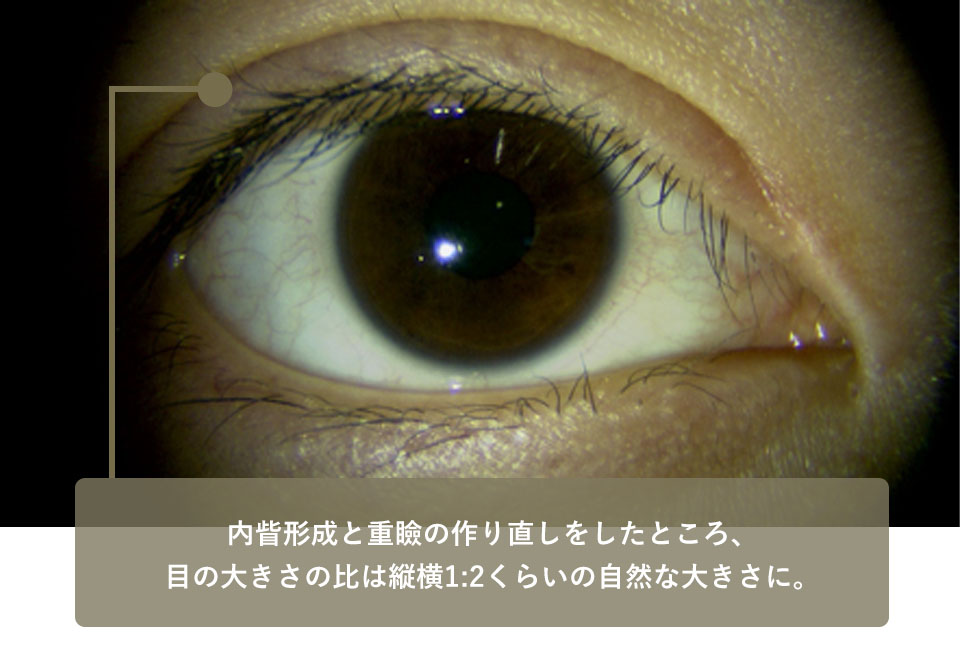

| Before surgery | The double eyelid is too high and there is a mongolian fold with excess skin below it, making the eye size 1:1 in length and width, which is unnatural. |

|---|---|

| After surgery | After an Eyebrow lift and a double eyelid makeover, the eye size ratio was about 1:2 lengthwise and widthwise, which is natural. |